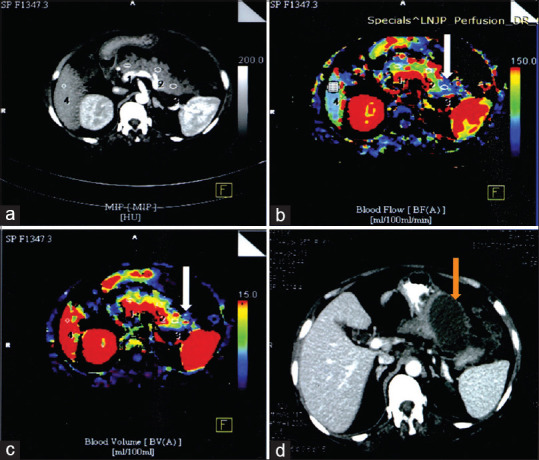

Methods: A prospective cross-sectional study was conducted on 50 SAP patients who underwent PCT within 72 h of symptom onset. PCT was performed to assess pancreatic blood flow (PBF), pancreatic blood volume (PBV), mean transit time, and time to peak. Follow-up contrast-enhanced CT was performed at 2 weeks to confirm necrosis. Perfusion parameters were compared between necrosis and non-necrosis groups. Diagnostic performance metrics (sensitivity, specificity, positive predictive value [PPV], and negative predictive value [NPV]) were calculated.

Results: Perfusion defects were identified in 21 patients, with 18 (85.7%) subsequently confirmed to have necrosis. The necrosis group had significantly lower PBF (35.49 ± 21.62 mL/100 mL/min) and PBV (11.16 ± 4.84 mL/100 mL) than the non-necrosis group (125.72 ± 50.37 and 17.67 ± 3.80, respectively, P < 0.05). PCT achieved 100% sensitivity, 90.6% specificity, 85.7% PPV, and 90.6% NPV. Optimal cutoff values were BF ≤57.87 and BV ≤14.90.